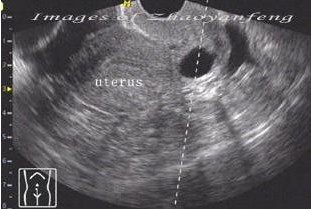

宮頸囊腫二維聲像圖定位

宮頸囊腫的B超診斷表現:檢查時可以看到宮頸表面突出多個大小不一的青白色囊泡(并非紫色),內含黏液,小的有米粒大,大的有玉米粒大,有的可以長得很大,突出于宮頸表面,甚至到達陰道口,根部與宮頸之間有蒂相連,常合并有宮頸肥大。